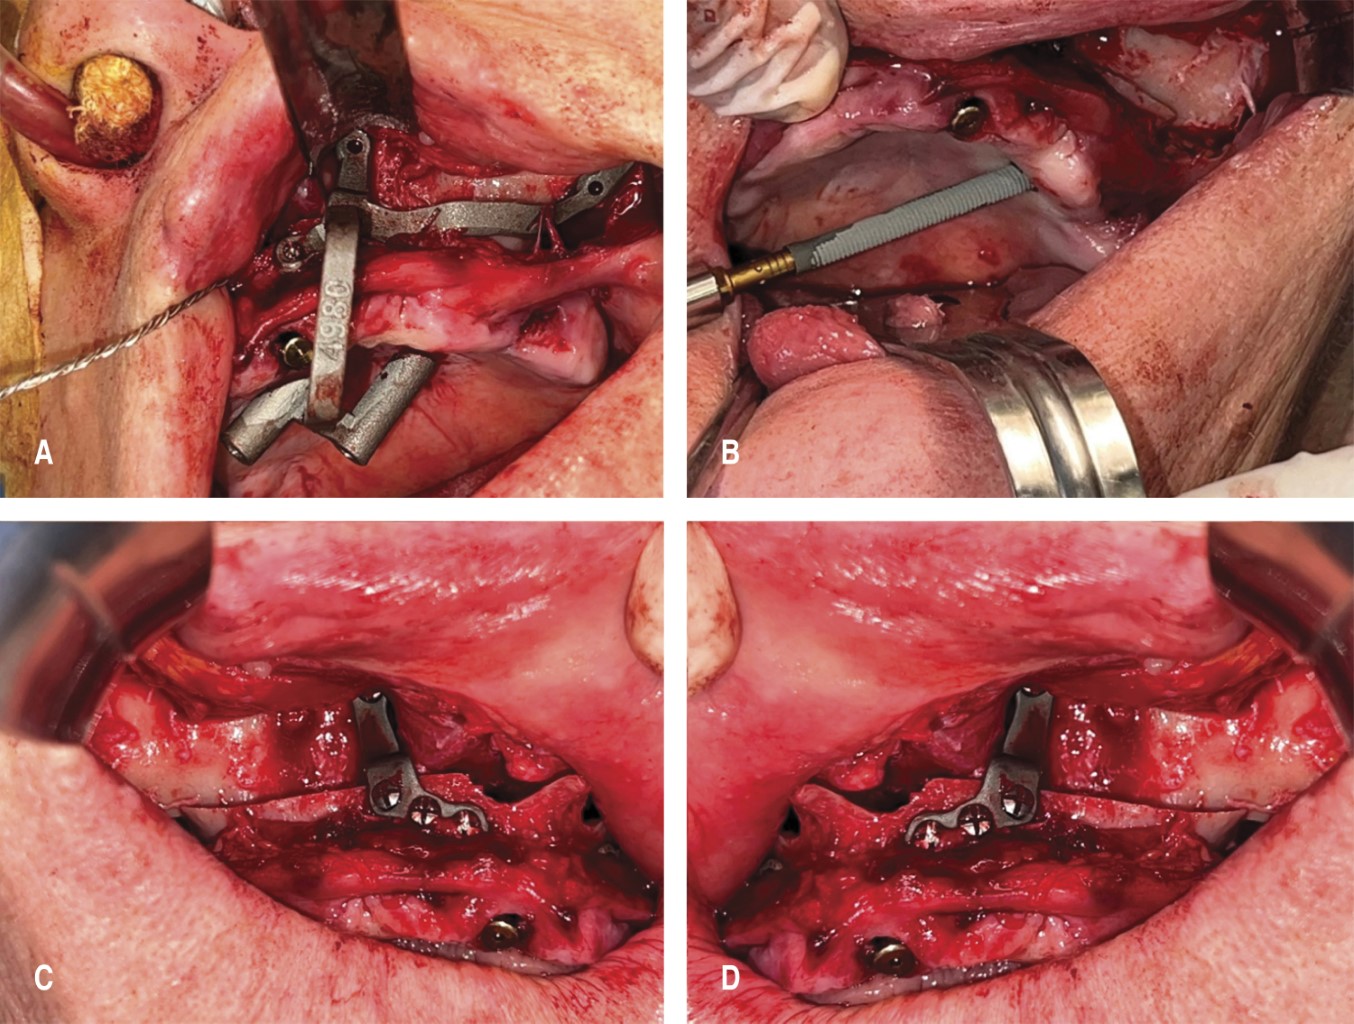

Las etapas de la cirugía incluyeron:

• 1. Una incisión en fondo de surco horizontal de canino a canino de grosor mucoperióstico para exponer áreas clave del maxilar y el complejo cigomático.

• 2. Osteotomías maxilares mediante la utilización de guías quirúrgicas personalizadas para realizar cortes precisos en el hueso maxilar (Figura 4).

• 3. Fractura Le Fort I controlada del maxilar y su reubicación con avance programado, fijado con placas y tornillos de osteosíntesis según el protocolo dual utilizado por el autor. Se prestó atención a la integridad de la mucosa nasal y la membrana de Schneider, así como a la optimización de la proyección de la punta de la nariz mediante el soporte de la región nasolabial para lograr un buen resultado estético y funcional.

• 4. Colocación de implantes dentales y cigomáticos con guías de inserción personalizadas. Para los implantes cigomáticos se empleó un protocolo de doble guía/soporte. En este momento se colocan las placas de fijación de avance maxilar de forma definitiva (Figura 5).